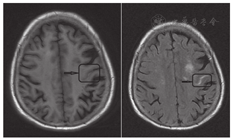

影像学检查:入院次日复查头颅CT示左侧额叶部分脑沟内高密度影,考虑少量SAH,较前变化不大。头颅MRI示左侧基底节区、左侧丘脑、左侧枕叶、双侧小脑半球可见多发小灶样T1低信号和T2高信号影,边界清晰(图2);弥散加权成像未见异常高信号影;双侧侧脑室周围可见轮缘状液体衰减反转恢复序列(fluid-attenuated inversion recovery, FLAIR)高信号,双额叶白质区可见多发小点片状FLAIR高信号影,边界不清;磁敏感加权成像可见左侧额部一粗大血管影,其内见高信号影(图3),另见左侧基底节区和双侧小脑半球多发小圆形低信号影;磁共振血管造影示颅内血管多发性狭窄,右侧大脑后动脉显影浅淡,远端分支减少(图4)。数字减影血管造影示左侧大脑中动脉M1段闭塞,右侧大脑后动脉P1段闭塞,左侧颈内动脉C5段轻度狭窄,右侧颈内动脉多处中至重度狭窄,双侧大脑前动脉多处狭窄,右侧大脑中动脉多处狭窄,双侧椎动脉多处狭窄,基底动脉中段多处狭窄,左侧大脑后动脉多处狭窄,未见静脉窦异常。